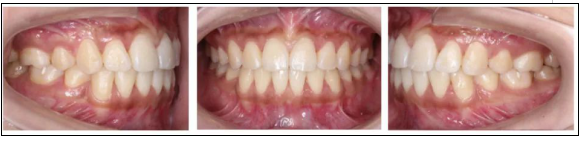

矯正后

正面觀突度改良,面部肌肉自然松馳,開唇露齒已糾正,唇齒關(guān)系改良;側(cè)貌明X改良,趨于直面型,頦部自然松馳。